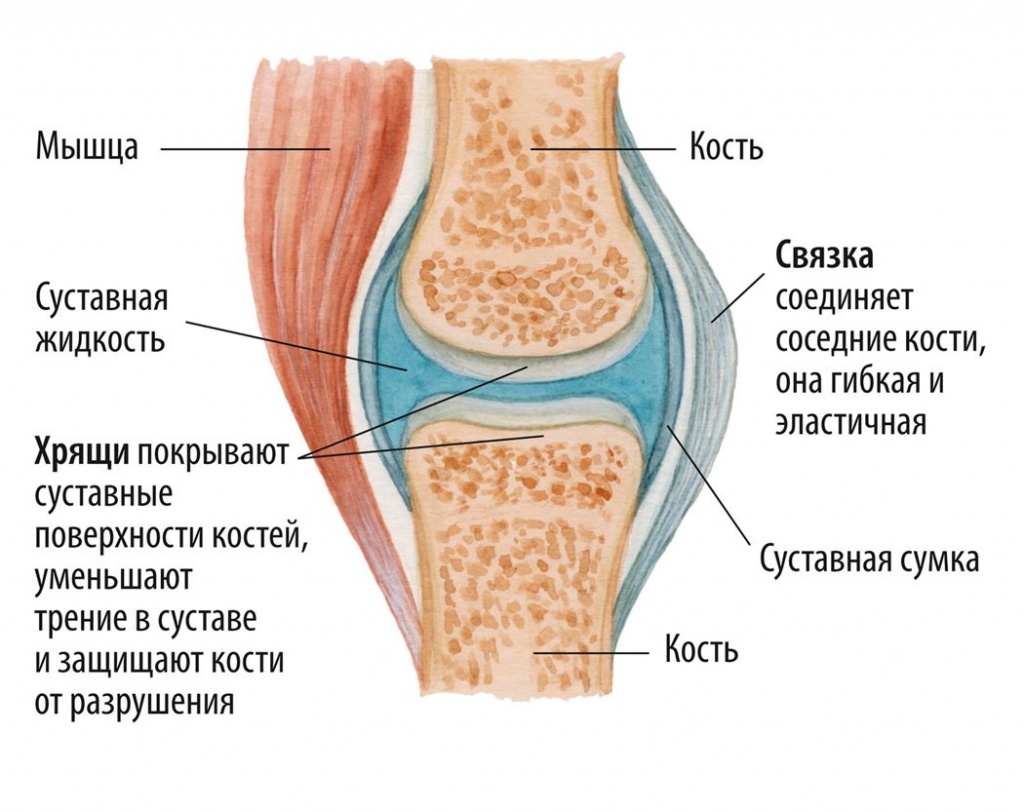

Суставная Жидкость и Головка Сустава: Обзор и Здоровье